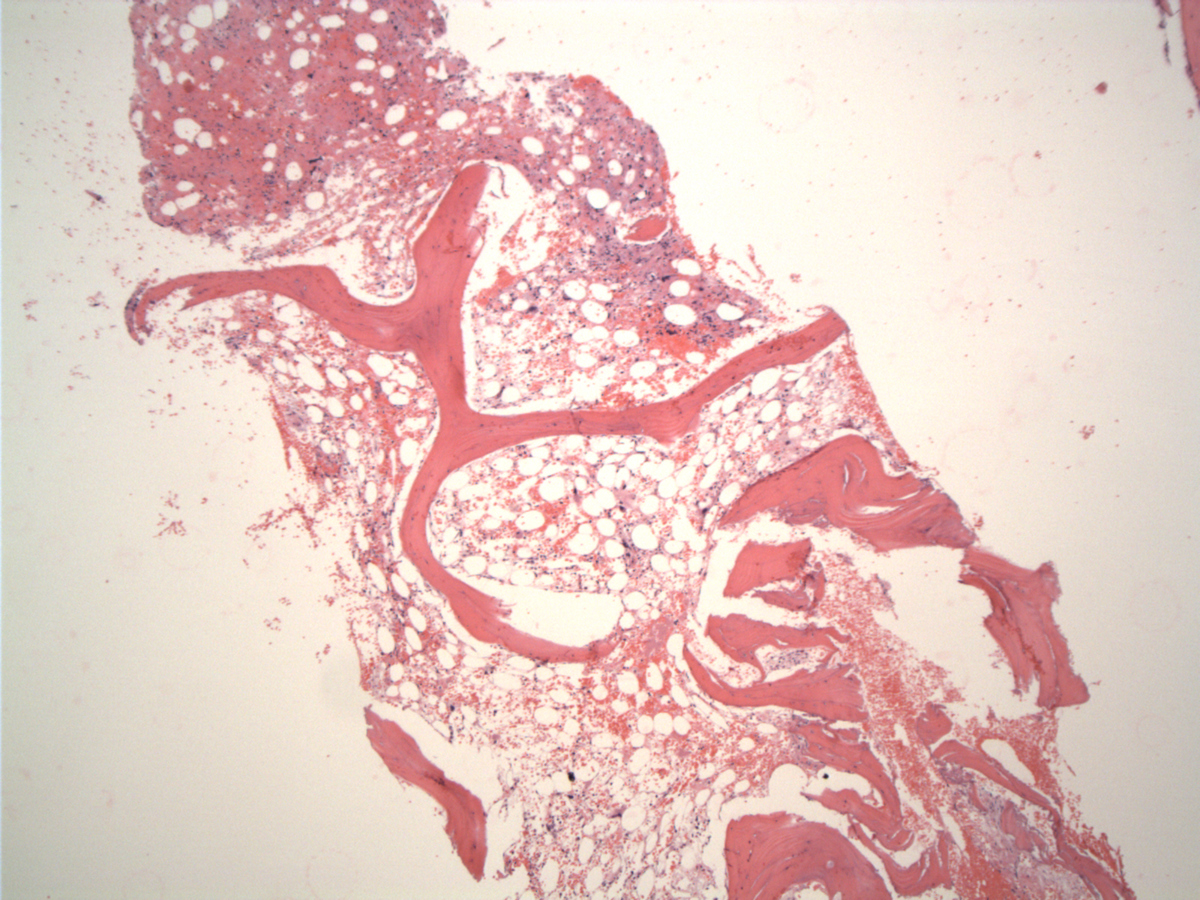

The formalin-fixed, paraffin-embedded biopsy showed hypocellular marrow with markedly decreased granulocytic and erythroid precursors, dyspoietic megakaryocytes, extensive stromal injury and rare interstitial atypical cells, medium to large size, with ovoid nuclei variably condensed chromatin, occasional prominent large eosinophilic central nucleoli and abundant cytoplasm. Rare Reed-Sternberg–like cell were seen but no lymphoid aggregate or fibrosis was identified. In the touch imprints the atypical cells have large or medium-sized hyperchromatic nuclei and large central nucleoli, abundant basophilic cytoplasm with eosinophilic granules. Peripheral blood shows pancytopenia with severe neutropenia, rare Döhle bodies and no circulating tumor cells.

| Bone marrow at presentation-day 1 | ![]() |

| Bone marrow day 9 | ![]() |

| Hypocellular marrow space with stromal injury | ![]() |